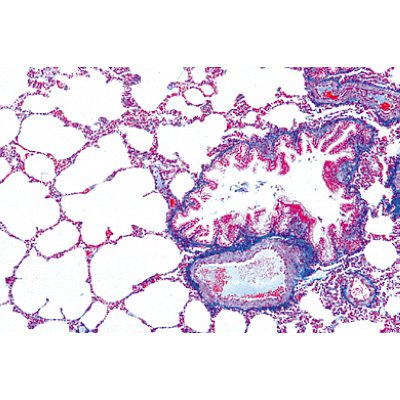

3B1004225